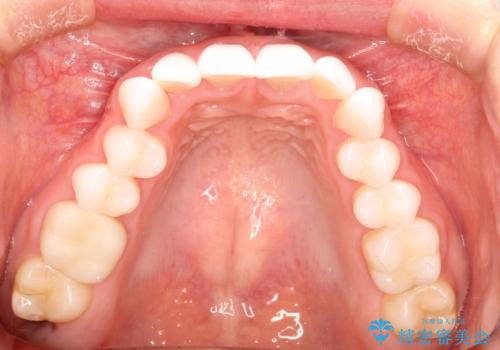

気になる前歯の歯並びをインビザラインで矯正

- 前歯の傾きと、ガタガタが気になるとのことで来院されました。

前歯の傾きや高さをシミュレーションで患者様と確認しながら、歯並びを仕上げていきました。